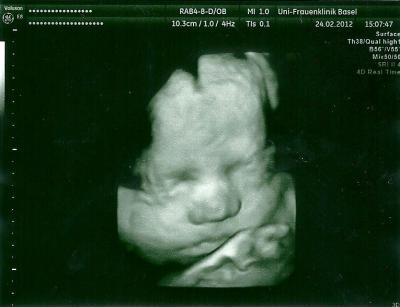

Wieder ein schönes Foto

von meiner kleinen Maus. Der Mund ist total von Papa und der ist natürlich ganz stoll. Ca. 1800g wiegt sie und wird per Kaiserschnitt geholt.

wow da sieht man ja schon ein wenig die "Fettschicht" die sie nun aufbauen. Süß sieht sie aus. Warum bekommst du einen KS? LG Diana